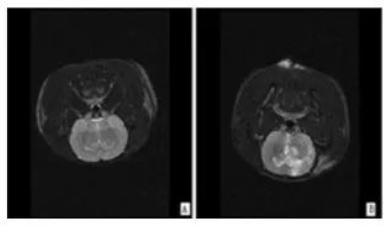

圖|大鼠腦卒中核磁共振圖像